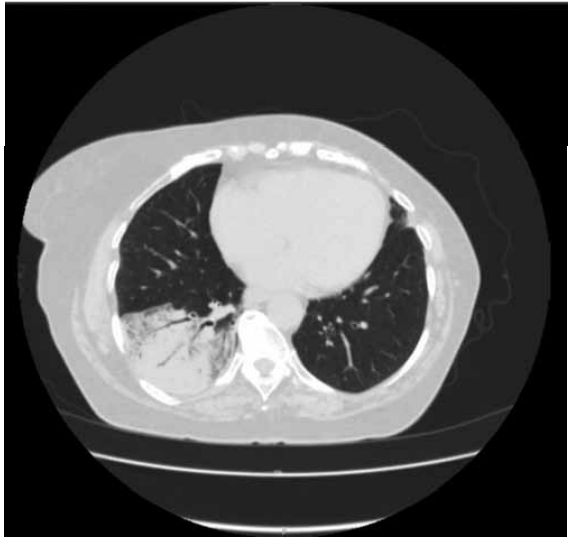

Ela realizou uma tomografia computadorizada de tórax:

(Arquivo pessoal; imagem usada com autorização)